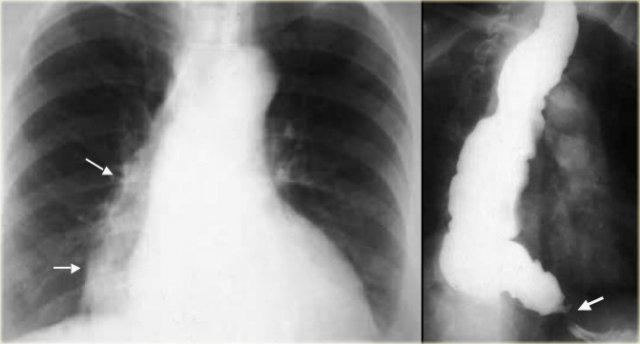

TRÁI: Thực quản giãn (mũi tên) biểu hiện là cấu trúc dài, bờ rõ nét song song với tim. PHẢI: Thực quản giãn thường lệch sang phải. Hẹp (mũi tên) tại khe hoành.

Achalasia

Hình ảnh chụp thực quản:

- Giãn thực quản kèm mất nhu động

- Hẹp thuôn nhẵn tại khe thực quản của cơ hoành

- Ung thư đoạn xa có thể giả dạng achalasia (giả achalasia)

TRÁI: CT cho thấy thực quản giãn (mũi tên) dẫn đến chỉ định chụp thực quản. PHẢI: Chụp thực quản cho thấy hẹp (mũi tên) tại mức khe hoành.